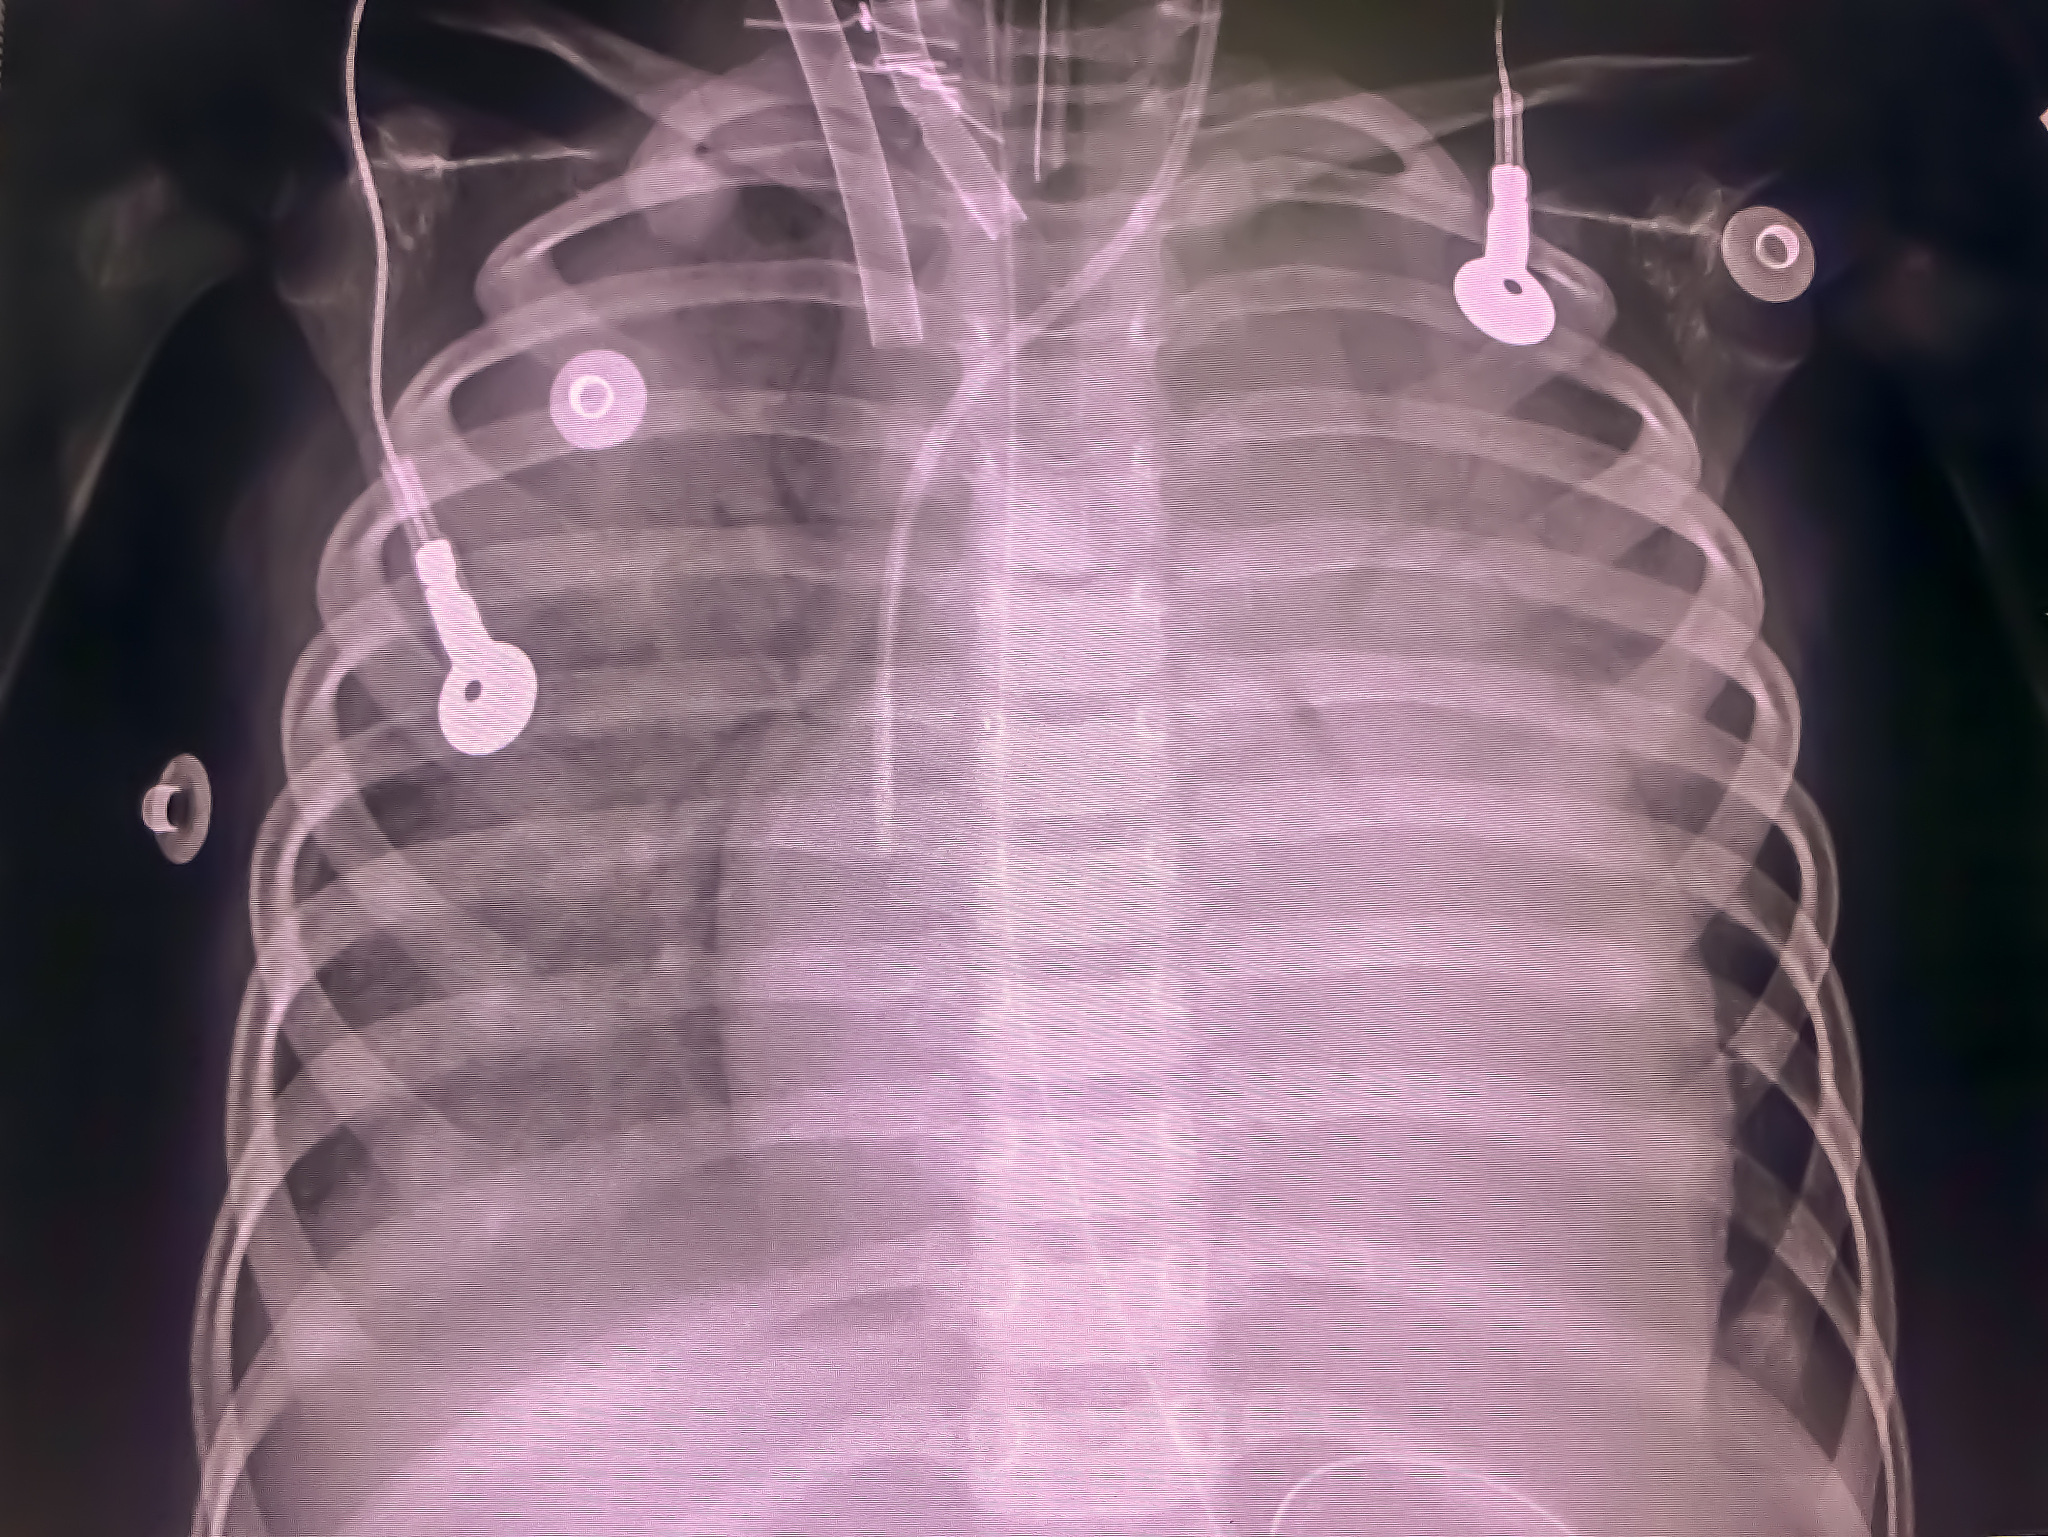

2. 术中监测:监测患者的生命体征,包括心率、呼吸频率、血压、体温等,及时发现异常情况并及时报告医生。监测患者的血氧饱和度,必要时给予氧气供给。

闭合性胸腹部损伤合并创伤性脾破裂腹腔镜探查术中护理要点